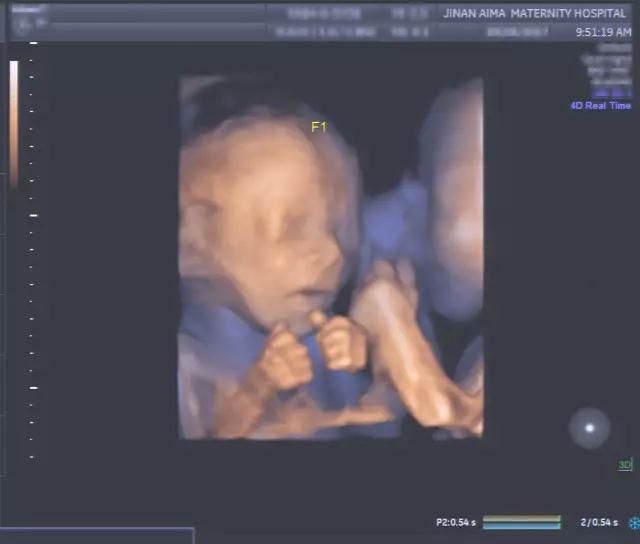

“看到宝宝们在子宫里的亲密举动,这种感觉真是太棒了。”宝妈欣喜地说。

艾玛妇产超声专家朱爱莲表示:“我们经常看到双胞胎宝宝脸部表情的细节,比如微笑和眨眼,还有彼此之间的互动,这是非常有趣、非常温馨的画面。同时,这种亲密的举动能对双胞胎的发育起到帮助作用,而且可能对她们出生后的情感交流有积极的影响。”

不仅如此,四维彩超(四维彩超)更重要的医学意义是通过清晰的画面对胎儿的体表进行检查,及早发现唇裂、脊柱裂,大脑、肾、心脏、骨骼发育不良等各种畸形情况,检测和发现各种异常。简单的说,四维彩超(四维彩超)的作用,就是从零岁起监测宝宝的发育情况,保障每个新生儿的健康!

济南艾玛妇产医院作为山东首家 妇产专科医院,直非常重视围产期保健及宝宝出生缺陷的预防,领先的美国GE-E8彩超成像设备和其他进配套设施,采用全容积四维TrueHD技术,能满足妇科、产科、盆底超声、生殖医学及母胎医学等各个领域的诊断需求,为您提供更精准的筛查检测数据。

四维彩超科作为艾玛妇产的特色科室,由具有二十年以上工作经验的专家、以及三甲医院影像科的超声专家组成,为宝妈及早发现胎儿缺陷、异常妊娠提供了强有力的多重保障。